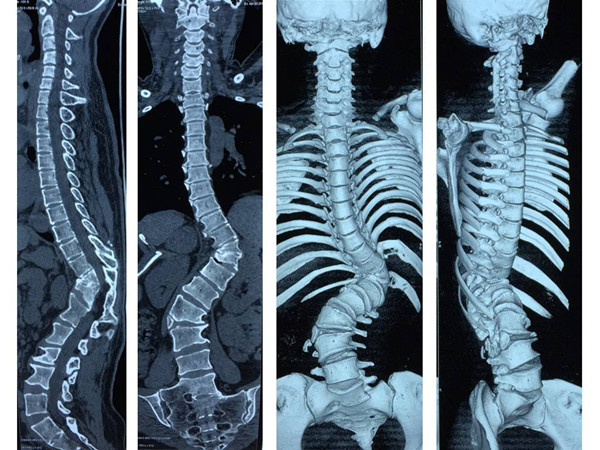

术前全脊柱CT三维重建

应用3D打印脊柱模型辅助手术

来自我省咸阳市的患者张某,因胸腰部脊柱畸形30余年,腰部疼痛1月慕名来我院求诊。患者为成年女性,诊断为先天性脊柱侧弯。病程长,儿时有过手术史,侧弯Cobb角度超过90度。入院后科内反复讨论,研读患者的影像学资料,并采用3D打印重现患者脊柱骨性结构(1:1)。在此基础上,制定了详细的术前计划及整体治疗方案。治疗过程中,采取骨性牵引2周,缓解手术矫形时神经肌肉血管的张力,降低手术风险,手术当天,由贺西京教授主刀,李浩鹏教授,王栋副教授,赵波、秦杰主治医师、王放住院总医师密切配合,在麻醉科及手术室的协助下,施行截骨矫形手术。术中诱发电位监护、自体血回输,唤醒试验、中心静脉压、外周动脉压监护、保温毯等措施保护患者的生命安全及神经功能。患者畸形严重,手术非常复杂,稍有不慎即有可能导致瘫痪,给患者和家属带来严重负担。贺西京教授、李浩鹏教授、王栋副教授等手术麻醉人员全神贯注,一丝不苟,连续手术8小时,患者脊柱畸形明显纠正,侧凸Cobb角纠正至20°,生命体征及神经功能完好,患者截骨矫形手术顺利完成。术后在我科护理和我院康复科医师的精心护理康复下,患者1周下地站立行走,顺利康复。术后无明显并发症,患者及家属对手术效果非常满意,现已出院。